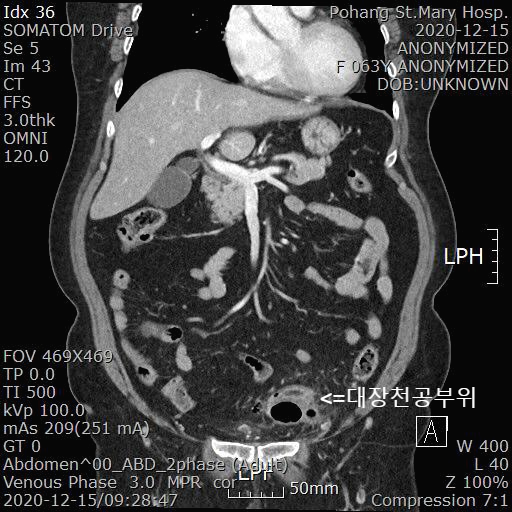

2020.12.14일 본원 소화기내과에 아랫배 통증을 주증상으로 내원하셨습니다. 복부 CT예약을 하고 다음날 2020.12.15일 검사를 진행했습니다.

[복부 CT]

About 5.5 x 4.5 x 2.5cm sized lobulated lesion at left supravesical space, just inferior to s-colon

-- thick enhancing rim with air-fluid level, with pericolic fat haziness

-- underlying multiple diverticulosis at s-colon

--> highly suggested acute diverticulitis with perforation, result in pericolic abscess formation, s-colon

복부 CT에서 sigmoid colon에서 약 5.5cm의 천공부위가 확인됩니다. 게실염 천공 가능성이 가장 높아 보입니다.